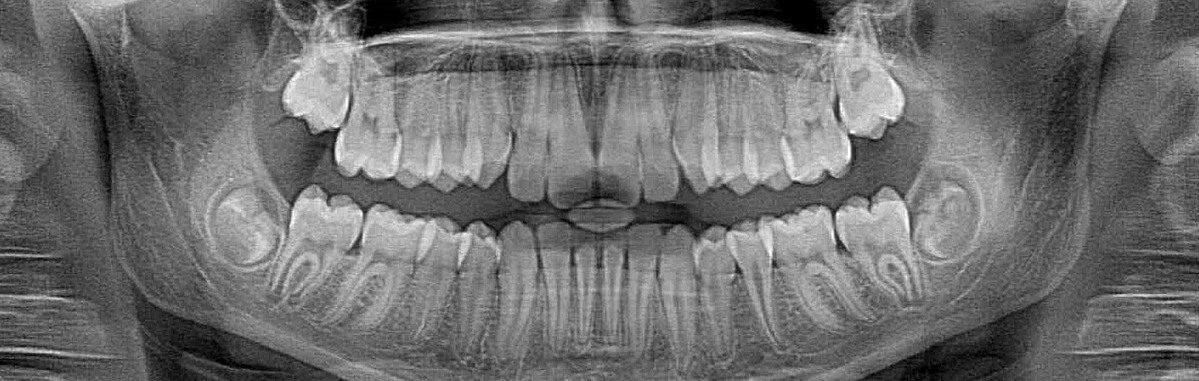

X-rays enable Dr. Sample to check the progress of your orthodontic treatment. In rare cases (only 2 percent), dental roots can shorten due to the pressure applied by braces, and the only way to make sure this isn’t happening is with x-rays. More commonly, a crowding problem might come up and treatment will need to be adjusted. Traditional x-rays expose patients to radiation, which is why you always wear a lead apron when the images are being taken. Thanks to advances in technology, there is now a safer way to take these images.

Film x-rays have been used in dentistry for decades. In the past few years, many forward-thinking orthodontists like Dr. Sample have invested in digital x-ray technology. Film x-rays cost a bit less than digital x-rays, but the increased exposure to film x-rays is more harmful to a patient’s overall health. Our digital x-ray emits as much as 85 percent less radiation than traditional x-ray technology.